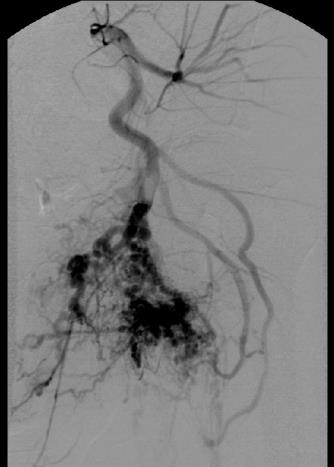

原则上首先阻塞大的供血动脉的远端,不要阻断它们的近端。包括使用渗透性栓塞剂(penetrating agent)如液体栓塞剂(如果你很勇敢/有经验/病人对潜在并发症有预期/有个好律师,就用酒精吧!不过我喜欢用Onyx和胶-glue)和微导管对大的供血动脉的分支逐次进行远端的栓塞,但要注意每个分支可能参与正常组织结构的供血。如果你对预计栓塞的分支供血分布有任何怀疑,避免用液体栓塞剂。完成主要大血管的末端栓塞后,再考虑是否进行其它分支的远端栓塞,因为一次性完成栓塞往往导致更多的并发症。 |